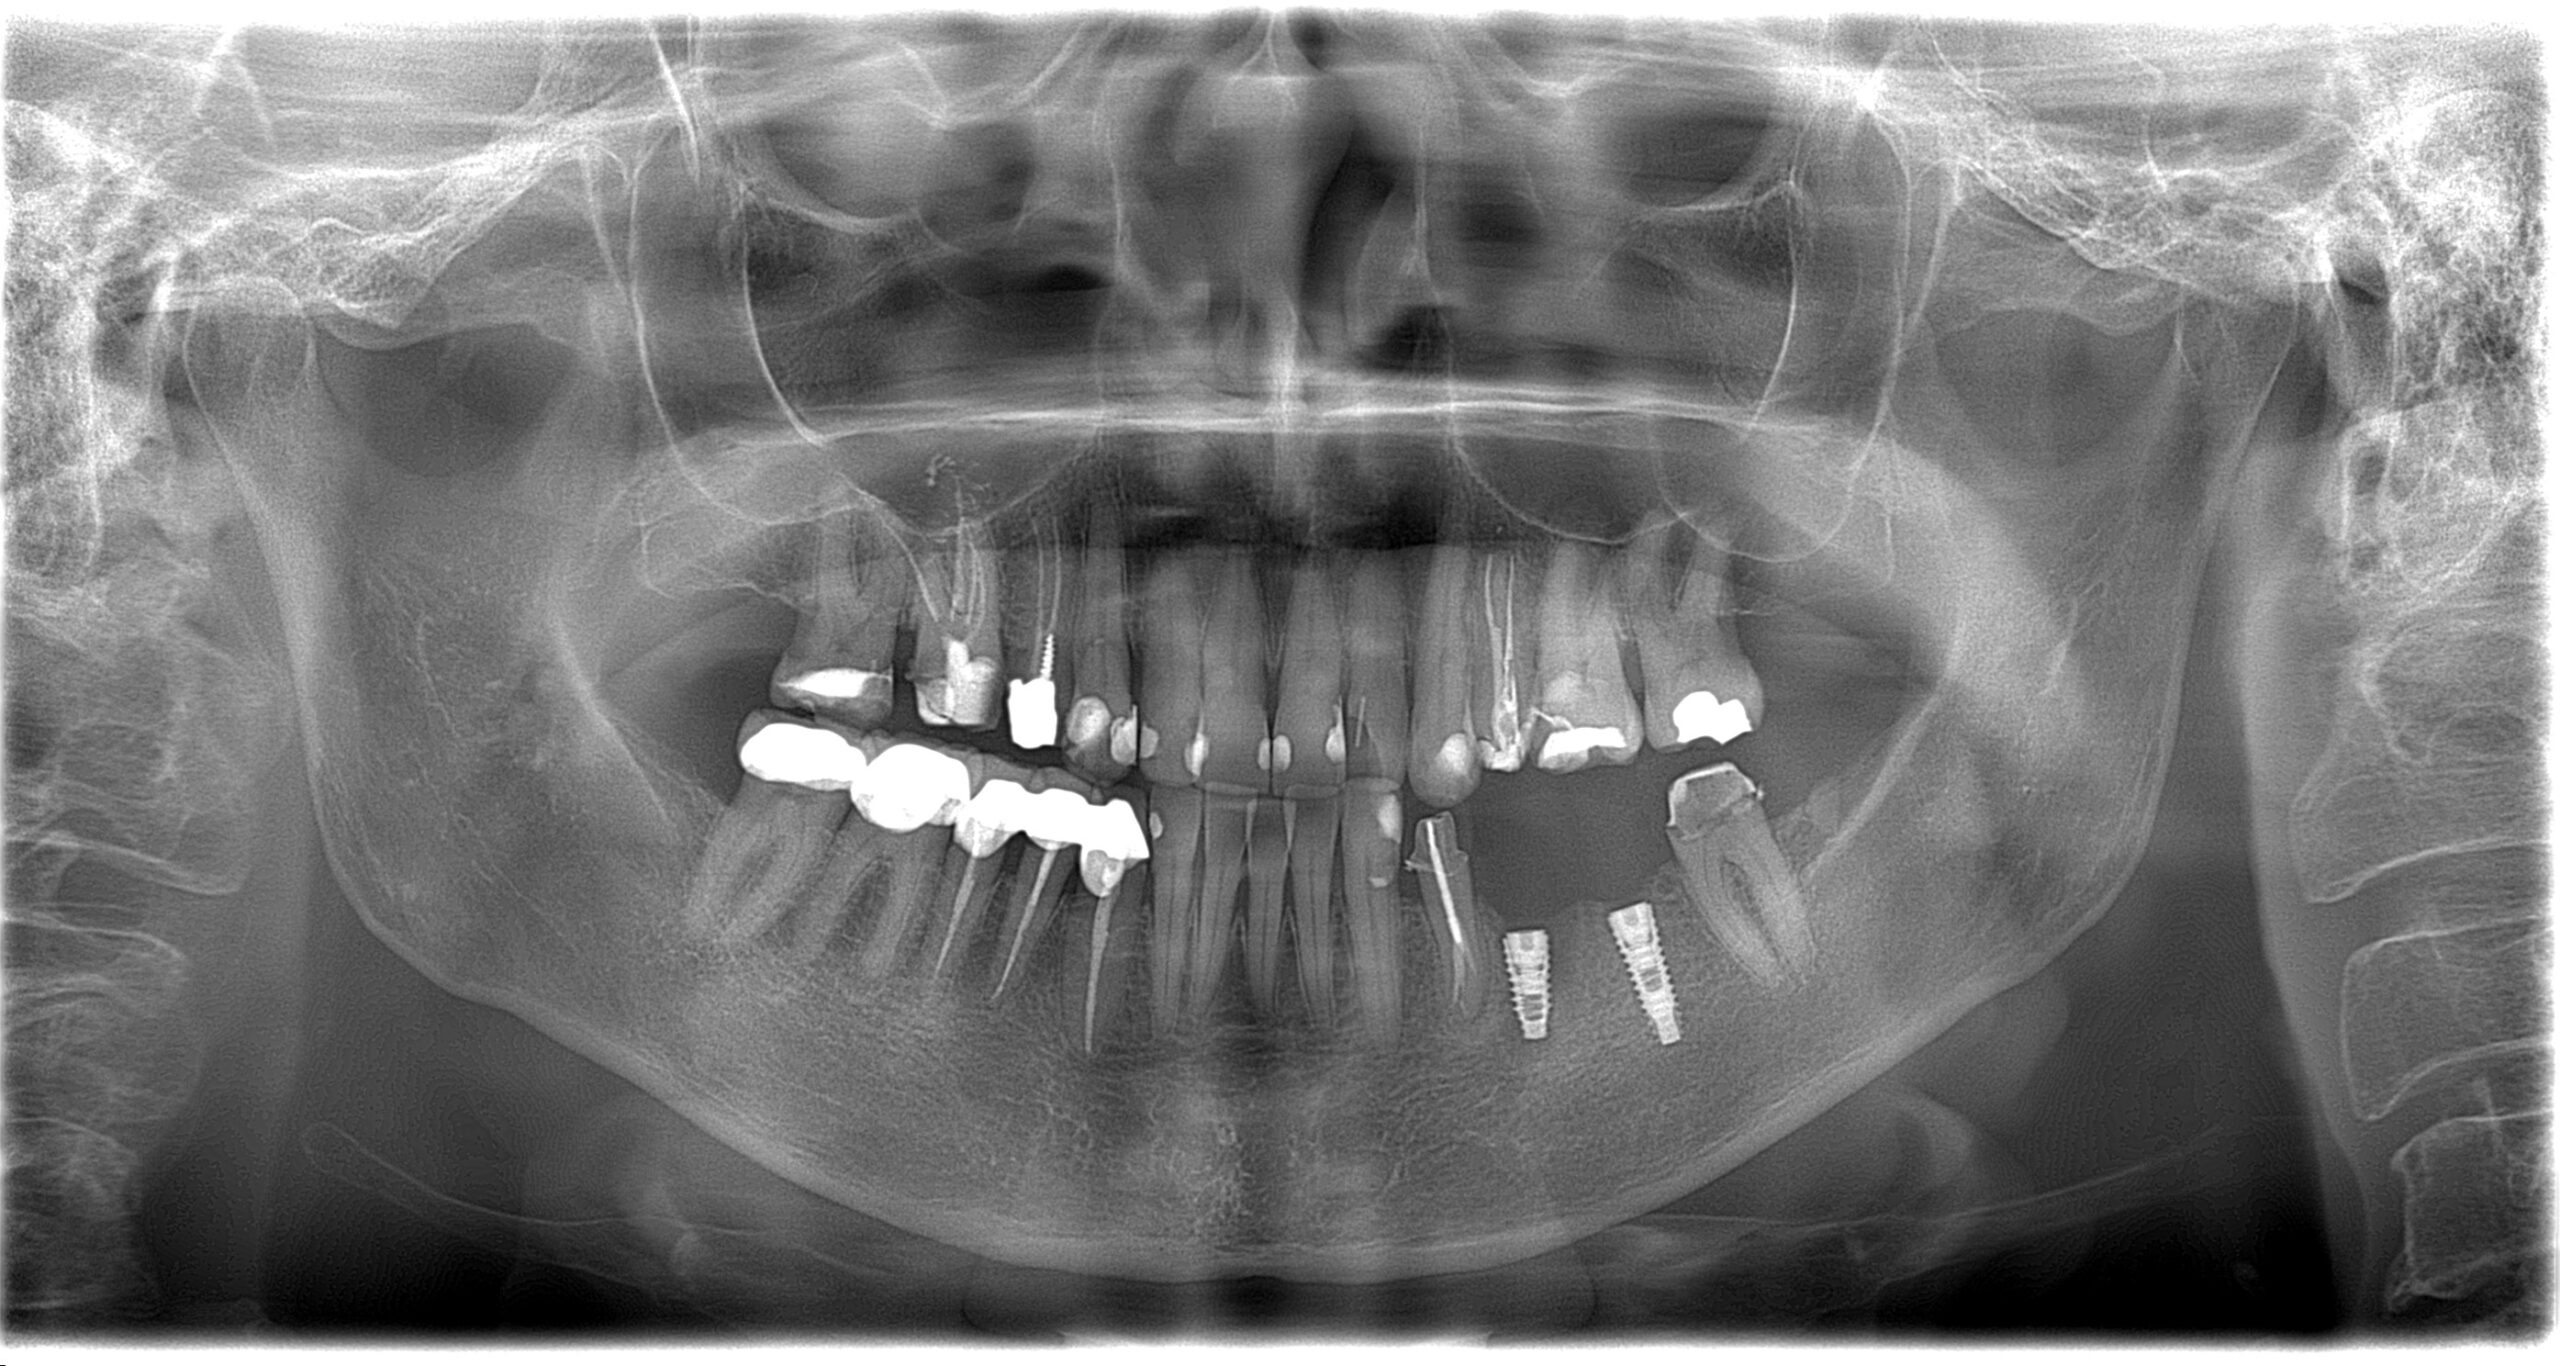

Імплантація